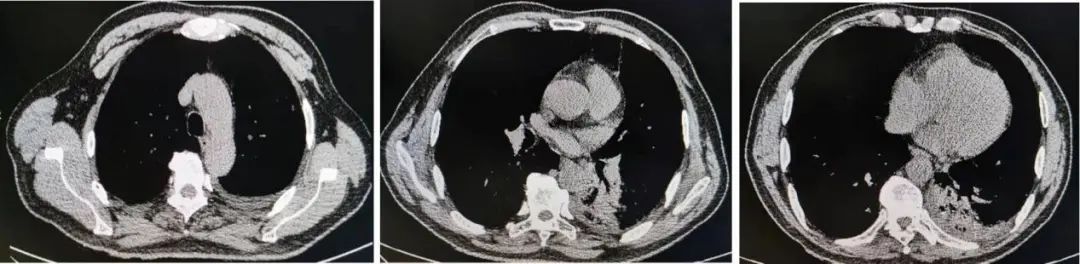

为了解肺炎影像学变化情况,我们复查了胸部CT(图6、图7)。

图6:6月24日胸部CT

图7:7月6日复查胸部CT,显示双肺炎症、双侧胸腔积液较前进展。